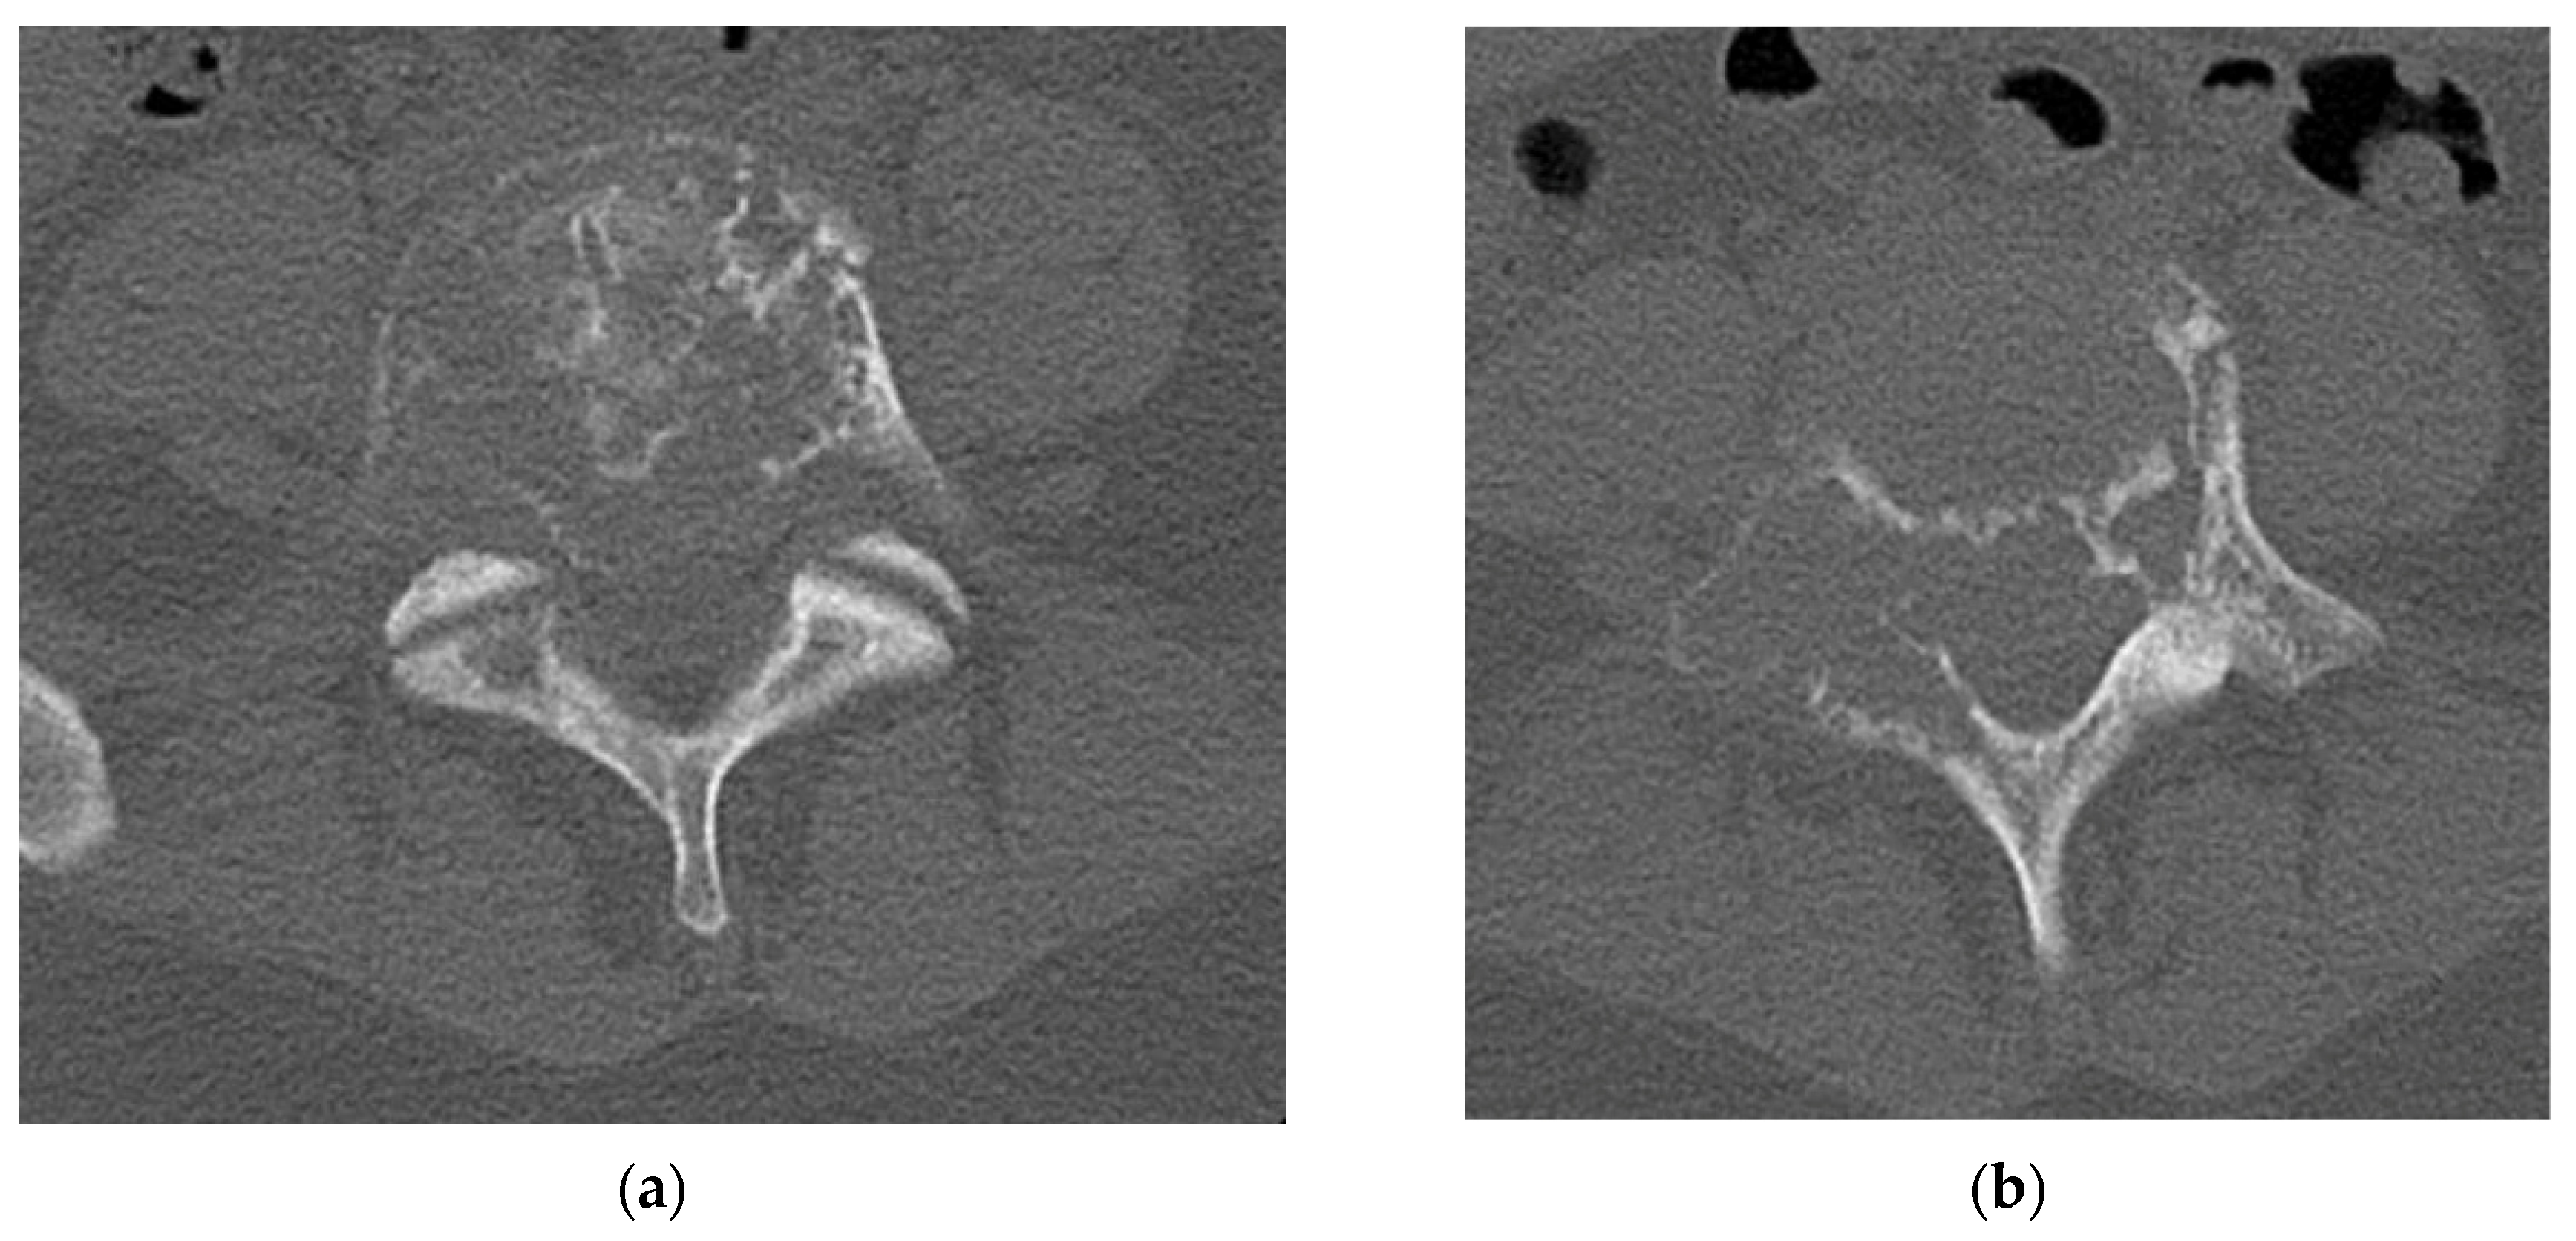

4.2.4. Computerized Tomography Scan